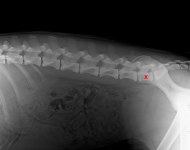

(2) 7 týdnů lat

(2) typ 3 I